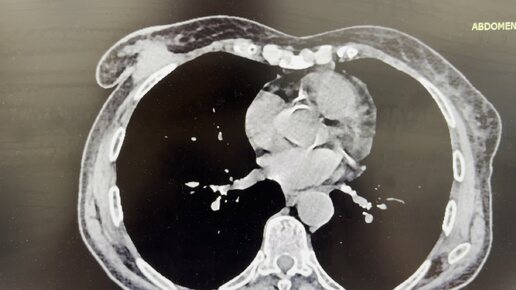

КТ с контрастом в диагностике рака молочной железы с метастазами в лимфоузлы